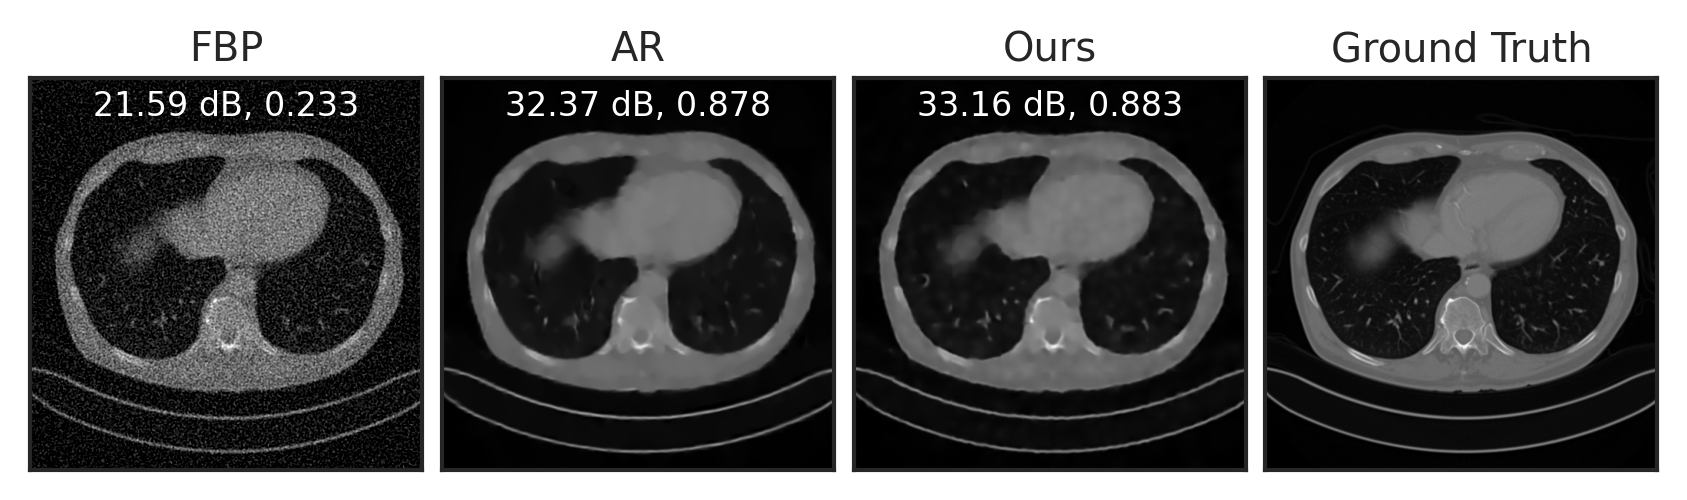

Sparse View Tomographic Reconstruction

Compressed Sensing

Deblurring